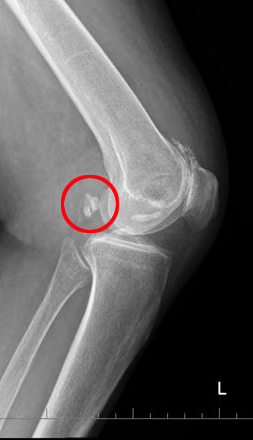

近日,76岁的果奶奶因饱受膝关节疼痛和活动受限的困扰来到首都医科大学附属北京潞河医院骨中心求医,主诉“左膝关节疼痛伴活动受限一个月”。骨中心主任刘亮在检查过程中发现果奶奶主要的问题在于膝关节游离体造成了关节的绞索与疼痛。但老太太因为患有严重的先天性心脏病,这无疑增加了治疗的难度和风险。面对这种复杂情况,骨中心与心脏中心通力合作,最终通过实施缜密的治疗方案,成功解决了老太太的膝关节问题,帮助她重拾起生活的希望。

果奶奶的膝关节因游离体的存在而产生剧烈疼痛,活动几乎受到完全限制,日常生活质量大大下降,甚至连简单的走路、上下楼都变得十分困难。更为糟糕的是果奶奶的心脏健康问题也同样严峻,严重的先心病使得任何手术都面临极高的麻醉风险。经过心脏中心心内科和心外科团队的仔细评估,建议果奶奶需要进一步心脏功能检查评估。虽然果奶奶对膝关节手术有强烈的需求,但她的心脏问题始终是手术能否顺利进行的最大障碍。

在了解了果奶奶的情况后,刘亮主任主动担当起了治疗重任。作为一位经验丰富的骨科专家,刘主任深知膝关节问题对患者生活质量的重要性,同时也充分考虑到高龄和心脏病因素,精心制定了个性化的治疗方案,决定采取局部浸润麻醉,这种方法能在确保患者安全的前提下最大限度减少麻醉风险,但是对术者却提出了更高的要求。刘主任运用膝关节镜技术,顺利地对果奶奶的膝关节进行了探查清理,并成功取出了游离体。整个手术过程非常顺利,术中出血仅为10毫升,手术时间也仅用了28分钟。

术后第一天,果奶奶顺利拔除引流管,X光复查后确认膝关节问题得到有效解决。果奶奶惊讶于膝关节症状的改善,她笑着说:“现在膝关节可以伸直,打弯也没有问题了,感觉自己年轻了不少!”在潞河医院的精心治疗和关怀下,果奶奶不仅膝关节恢复了健康,心脏问题也正在得到有效控制,重拾起生活的希望与信心。